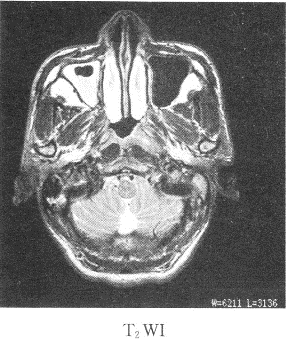

患者男性,39歲,因耳鳴,聽力下降來院,影像學(xué)檢查如圖所示

1.該患者最有可能的診斷是

正確答案:1.C;2.B;3.ABDE 解題思路:鼻咽癌我國以廣東省為高發(fā)地區(qū),男性多于女性,好發(fā)于鼻咽頂壁,其次為側(cè)壁,前壁和底壁極少。